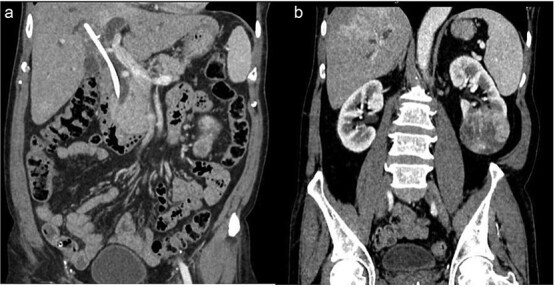

65岁男性,2年前因胆总管结石行内窥镜逆行胆管造影,发现左肾肿块,胆总管支架残留。影像学证实肾下极病变具有肾细胞癌(RCC)的特征,胆道扩张伴污泥和保留支架。患者接受了单期手术——左侧根治性肾切除术和开放式胆总管切除术,通过中线入路取出支架并清除胆道。组织病理学证实为嫌色性肾细胞癌。本病例说明了在资源匮乏的情况下,以患者为中心的双系统病理同时手术治疗的可行性。

A 65-year-old male presented with a left renal mass and a retained common bile duct stent from a previous endoscopic retrograde cholangiopancreatography 2 years ago for choledocholithiasis. Imaging confirmed a lower pole renal lesion with features of renal cell carcinoma (RCC) and dilated biliary tree with sludge and a retained stent. The patient underwent single-stage surgery-left radical nephrectomy and open choledochoduedenotomy-for removal of the stent and biliary clearance through midline approach. Histopathology confirmed chromophobe RCC. This case illustrates the feasibility of patient-centred manner simultaneous surgical treatment for dual-system pathologies in a low resource setting and.